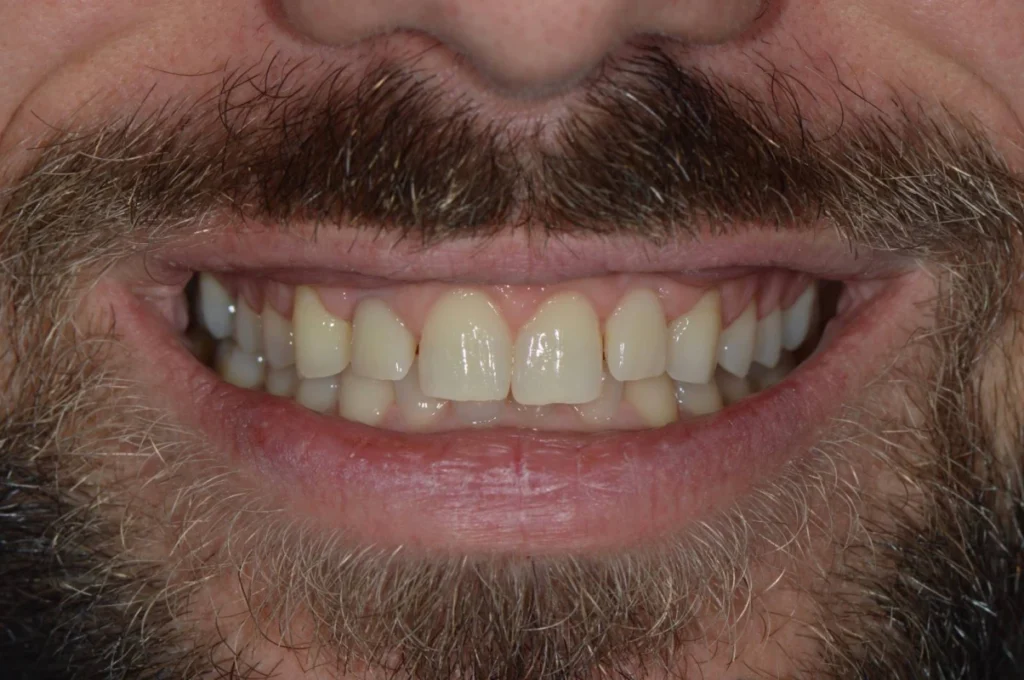

Monsieur R, 33 ans, se présente à la consultation pour améliorer l’esthétique de son sourire. Après une consultation approfondie, nous posons le diagnostic d’une « éruption passive incomplète ». Cela signifie qu’une partie des dents du patient est « cachée » par un excès de gencive. Cela donne l’impression de dents trop petites et d’une gencive trop visible lors du sourire. On appelle cela un « sourire gingival ».

Le traitement va donc consister en une intervention chirurgicale qui permettra de retirer cet excès de gencive pour rendre visible les dents dans leur intégralité. L’intervention réalisée sous anesthésie locale est totalement indolore et les suites opératoires assez limitées. Après quelques jours de cicatrisation, le résultat est déjà présent et le patient ravi d’avoir améliorer l’aspect de son sourire sans avoir touché à ses dents !